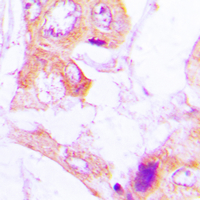

IHC (Immunohiostchemistry)

(Immunohistochemical analysis of ACC alpha (pS80) staining in human lung cancer formalin fixed paraffin embedded tissue section. The section was pre-treated using heat mediated antigen retrieval with sodium citrate buffer (pH 6.0). The section was then incubated with the antibody at room temperature and detected using an HRP conjugated compact polymer system. DAB was used as the chromogen. The section was then counterstained with haematoxylin and mounted with DPX.)